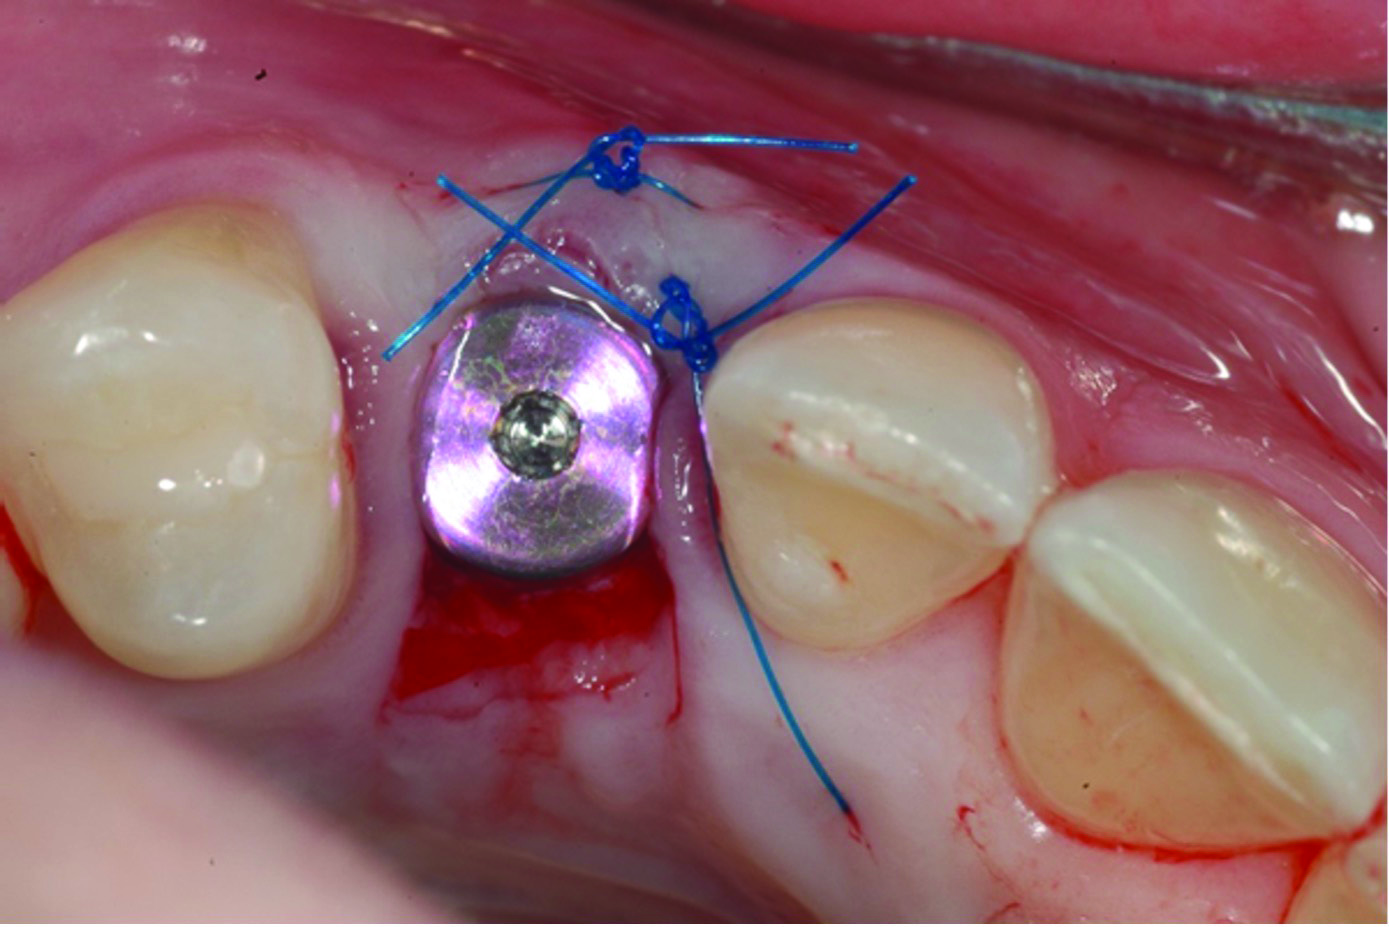

Fig 6 through Fig 8. Example of increasing KMW with an APF at implant uncovery. Fig 6: initial presentation showing lack of KMW; Fig 7: healing abutment placement with APF; Fig 8: 2 months post-treatment. (The dotted lines indicate the MGJ.) Fig 9 through Fig 11. Example of increasing KMW with an APF and FGG at implant uncovery.

Fig 10: healing abutment placement with FGG; Fig 11: 2 months post-treatment.